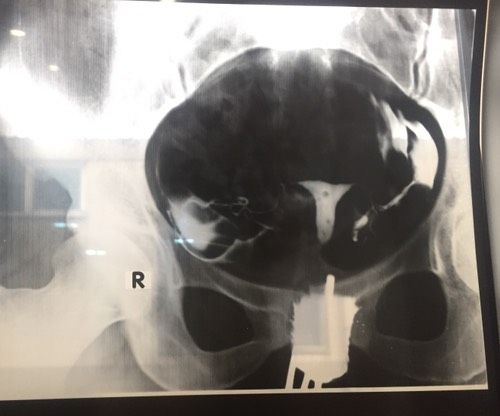

Рентген труб.Девочки добрый день, к гинекологу попаду только через несколько дней, помогите разобраться как вы считаете все ли в порядке?

Трубы проходимы но луче всё таки к врачу.

Ой лучше дождитесь гинеколога. Я вот первый раз такой снимок вижу и как по мне то проходимость хорошая)